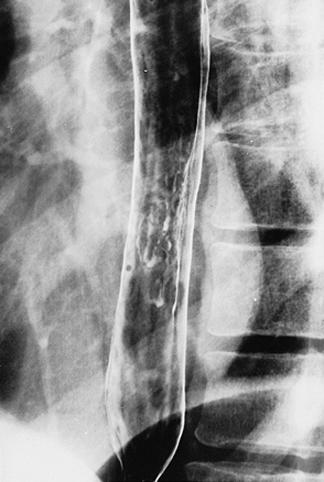

악성종양과의 식별이 곤란하였던 만성의 난치성 식도궤양(단순성 궤양의심)

염증성 및 궤양성질환/단순성궤양

식도/하

X-P

20~24